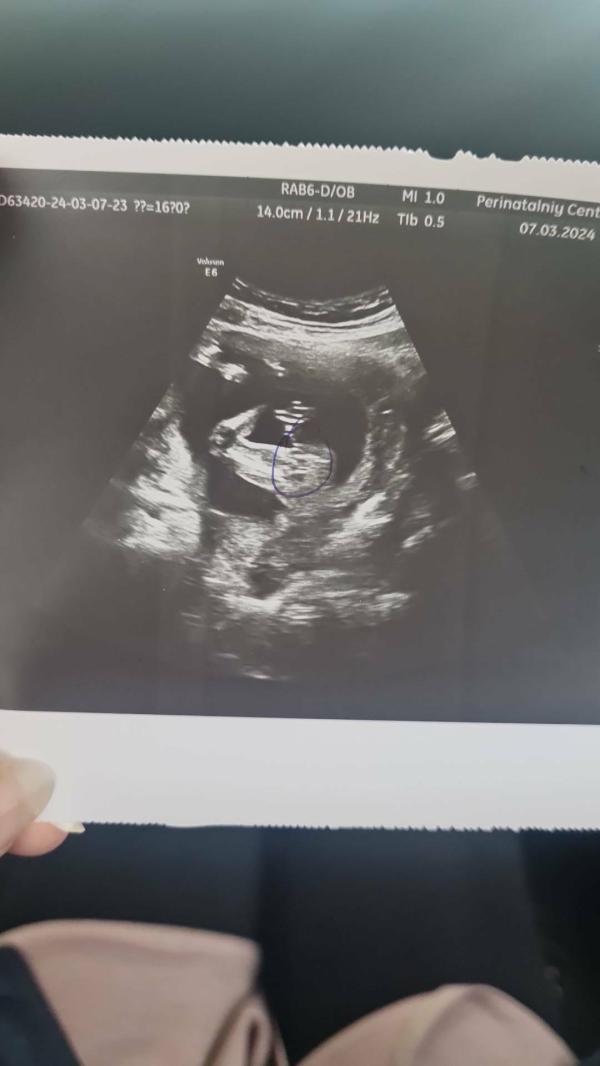

Ну вот наконец-то добрались руки. До 15 недели был мальчик Пётр, стала девочка 🤣

7 марта узнала, все еще пока не могу привыкнуть)